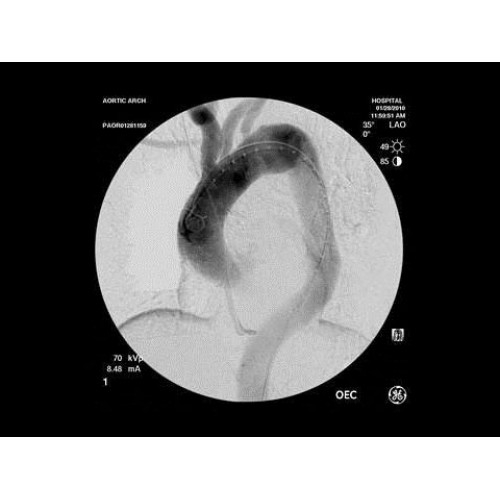

Инновационная мобильная С-дуговая система для интраоперационной визуализации с высоким разрешением. Обеспечивает хирургов качественным изображением в реальном времени при минимальной лучевой нагрузке. Усовершенствованная эргономика позволяет легко позиционировать аппарат в условиях операционной. Поддерживает интеграцию с современными хирургическими навигационными системами.

Передовая рентгенохирургическая система GE OEC 9900 Elite представляет собой инновационное решение для проведения широкого спектра малоинвазивных вмешательств. Это оборудование премиум-класса сочетает высочайшее качество визуализации с интуитивно понятным управлением, устанавливая новые стандарты в области интраоперационной рентгеноскопии.

GE OEC 9900 Elite оснащен революционной системой визуализации, обеспечивающей кристально четкое изображение анатомических структур. Интеллектуальная система автоматически адаптирует параметры исследования под конкретную хирургическую задачу, обеспечивая оптимальный баланс между качеством изображения и лучевой нагрузкой. Особое внимание уделено удобству работы операционной бригады.

В операционной практике GE OEC 9900 Elite демонстрирует исключительную эффективность при проведении сложных малоинвазивных процедур. Оборудование позволяет значительно сократить время вмешательства и повысить его безопасность для пациента. Многие хирурги отмечают улучшение точности операций и комфорт работы с системой.

В ведущих медицинских центрах GE OEC 9900 Elite успешно применяется для проведения сложных кардиологических, нейрохирургических и ортопедических вмешательств. Система доказала свою эффективность при выполнении стентирования коронарных артерий, эмболизации сосудов головного мозга и вертебропластики. Многие учреждения отмечают повышение качества операций после внедрения этого оборудования.